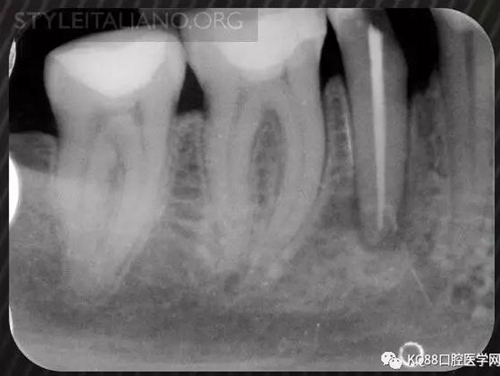

Img. 3 - The frequency of post-endodontic pain is higher in teeth with periapical or periradicular lesions. Infected debris can be forced in the periradicular tissue through a resorpted apex, thus generating acute inflammation. Creating a glide path prior to instrumentation and using a step-down technique can reduce the amount of extruded debris.

Img. 4 - Case 2: This necrotic first mandibular molar was treated in one visit, and the patient complained of post-operative pain. Analgesics and antibiotics were prescribed, and occlusion relieved. Symptoms disappeared after two days, and a radiographic follow-up after two years showed healing of the periradicular lesion.